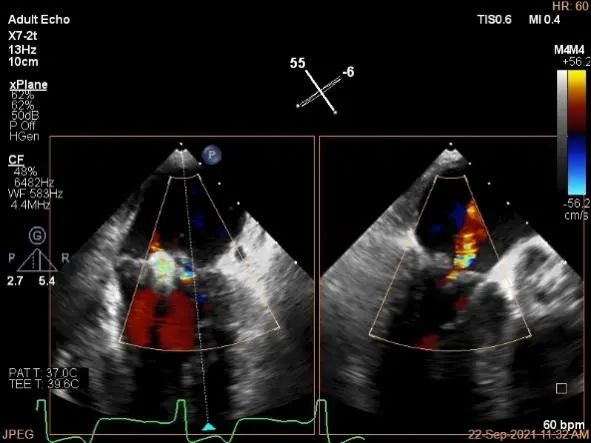

术中超声

P2区脱垂,宽14.8mm,Gap:3.3mm

3D-color,返流重度,3+级

麻醉状态下左肺静脉血流频谱

MVA:6.67cm²

房间隔穿刺点选择

穿刺高度:4.3cm